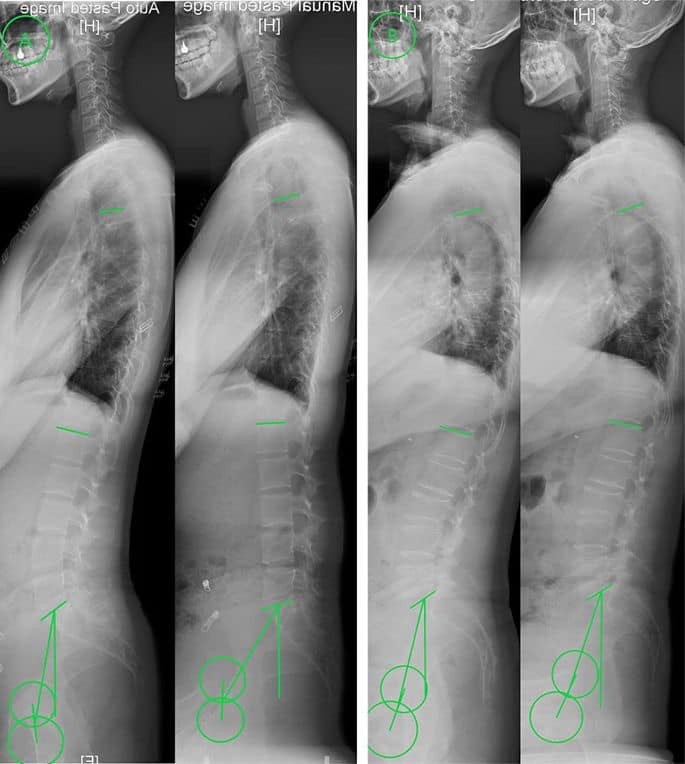

➤ La alineación sagital de la columna ha atraído atención en el campo de la cirugía de deformidades de la columna durante décadas. Sin embargo, los datos emergentes respaldan la importancia de restaurar la lordosis lumbar segmentaria y la forma de la columna lumbar de acuerdo con la morfología pélvica cuando se abordan quirúrgicamente patologías lumbares degenerativas como la enfermedad degenerativa del disco y la espondilolistesis.

➤ La distribución de la lordosis caudal (L4-S1) y la lordosis craneal (L1-L4) como porcentaje de la lordosis global varía según la incidencia pélvica (PI), y la lordosis cefálica aumenta su contribución a la lordosis total a medida que aumenta la PI.

➤ La fusión espinal puede provocar deformidad iatrogénica si se realiza sin prestar atención a la magnitud de la lordosis y la ubicación en la columna lumbar.

➤ Una base sólida de conocimiento con respecto a la alineación sagital espinal óptima es beneficiosa al realizar una cirugía de columna lumbar, y la planificación y ejecución cuidadosas de las fusiones lumbares con un enfoque en la alineación pueden mejorar los resultados de los pacientes.